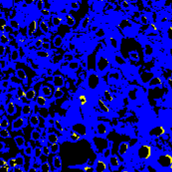

To investigate the impact of the proposed co-training and colorization methods, we validate the effectiveness of each module on the MoNuSeg dataset. Considering that Voronoi labels provide more shape supervision information than point annotation, we regard the model that jointly uses the point annotation and the Voronoi label as the baseline, and mainly evaluate the improvement of each module upon this baseline in Table III. Model A utilizes only point annotation and Voronoi labels with cross-entropy loss. For a fair comparison with co-training, we employ two separate models which have the same architectures for co-training and average the predictions of the two models in inference. Model B further adopts the cluster label. It can be seen that the cluster loss is beneficial in segmenting overlapping nuclei, improving the from 60.20% to 72.48% and the AJI from 43.01% to 51.77%, which indicates that simply using the point annotation and the derived Voronoi labels cannot provide sufficient supervision for the nuclei segmentation due to the lack of boundary and area information. However, the cluster labels generated by the -means algorithm cannot separate close nuclei which would introduce distraction to the training process, as shown in Fig. 1. To address this challenge, Model C utilizes the co-training strategy that the two models facilitate each other in a bootstrapping way to eliminate the distraction brought by the cluster labels. As expected, co-training brings a consistent improvement in all metrics, including an 1.19% increase to AJI. We believe that co-training compensates for the loss of supervision information in the uncertain regions in the cluster label, and the probability map with EMA by another model provides more precise and robust supervision in the nuclei boundary. Visualization of the segmentation results can be found in Fig. 3, and it can be seen that with the co-training strategy, the model can achieve more accurate results, especially in the nuclei boundary area. Model D involves colorization as a proxy task to implicitly learn to be self-aware of the nuclei boundary. Instead of directly coloring the H-component (Fig. 4(a)) to the H&E map (Fig. 4(d)), we use the segmentation probability map (Fig. 4(b)) as the input of the colorization network, which can help us to boost the segmentation accuracy. The experimental result shows that integrating the colorization tasks could not only improve the by 1.54% and AJI by 3.24%, but also promote Acc by 0.18% without dropping F1 score, proving that the colorization task has a significant guiding effect on nuclei segmentation. In Fig. 4(c), the improvement of colorization in the nuclei boundary area can also be observed. In general, the four modules used in our method have complementary advantages. By minimizing the weighted sum of the four losses, the proposed framework can distinguish between nuclear and non-nuclear to the greatest extent.